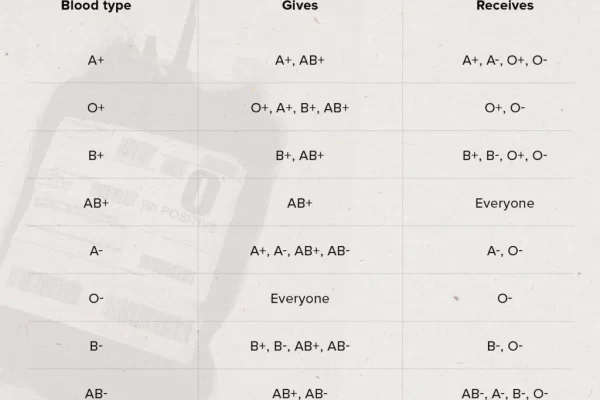

Introduction Blood is one of the most important fluids in living organisms’ bodies. It is a vital part of the circulatory system. A positive blood …